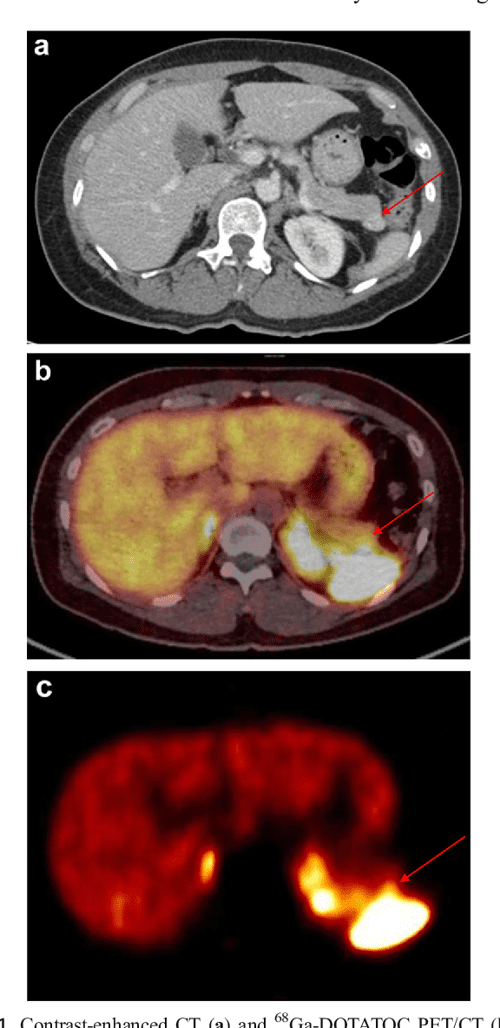

Pancreatic neuroendocrine tumor of the tail, invading the spleen (red Neuroendocrine Tumor Spleen The spleen contained a metastatic lesion 1.0 cm in diameter, consistent with a primary neuroendocrine tumor of the pancreas. Pancreatic neuroendocrine tumors (pnet) are rare, often indolent malignancies. Neuroendocrine neoplasms (nens) are a group of heterogeneous tumors with neuroendocrine differentiation that can arise. Pnet are classified as functional or nonfunctional. Neuroendocrine tumors start in the endocrine. The tail of the. Neuroendocrine Tumor Spleen.

Spleen Scan for 68GaDOTATOC PETPositive Pancreatic Tail Lesion Neuroendocrine Tumor Spleen The purpose of this article is to provide a review of the use of 68 ga tetraazacyclododecanetetraacetic. Pancreatic neuroendocrine tumors (pnet) are rare, often indolent malignancies. The tail of the pancreas is on the left side of the abdomen next to the spleen. The spleen contained a metastatic lesion 1.0 cm in diameter, consistent with a primary neuroendocrine tumor of. Neuroendocrine Tumor Spleen.